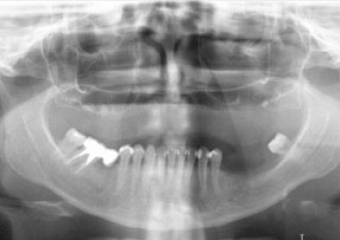

Raio X inicial